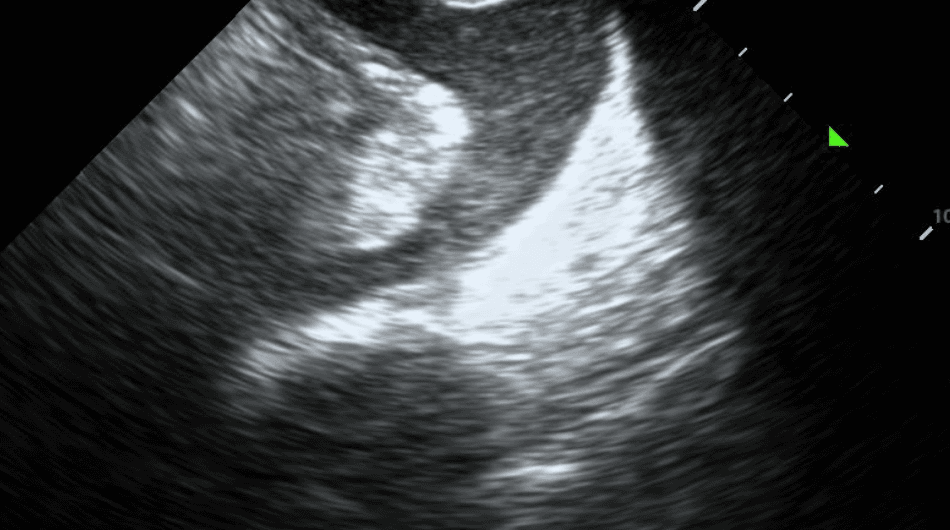

Secondly, you will see a consolidated lung sitting in the effusion. Please refer to our post on consolidations to learn what consolidated lung looks like. If the effusion is large, the consolidated lung will appear to float in the effusion - resembling a jellyfish swimming in the ocean. This is referred to as the “jellyfish sign.”

Estimating the size of a pleural effusion can help determine if, when and where the effusion can be drained. Effusion size may be qualitatively classified as small, medium or large. If there is a “jellyfish sign,” the effusion is at least moderate to large in size.